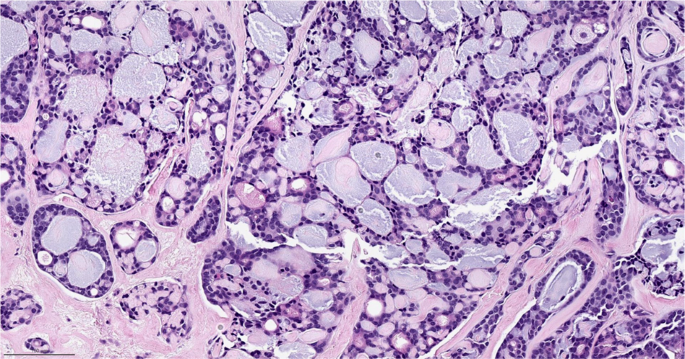

Adenoid cystic carcinoma

Adenoid cystic carcinomas are a salivary gland-type tumor with low malignant potential composed of both myoepithelial and epithelial cells51. Classic adenoid cystic carcinoma has a cribriform pattern and a basophilic matrix (Fig. 7). The tumors commonly have MYB-NFIB fusions but can also have MYBL1 rearrangements or MYB amplification52. Three subtypes have been described, classic adenoid cystic carcinoma, by far the most commonly diagnosed form of this subtype, and the less common, more aggressive subtypes: solid basaloid and high-grade transformational51,53. These tumors commonly present as a palpable mass in an older patient. Despite their triple-negative phenotype, prognosis for classic adenoid cystic carcinoma is excellent, and surgery is generally curative. Notably, tumors of similar histology and molecular phenotype arising in the salivary gland have a very different clinical behavior. Multiple retrospective series have shown no to marginal benefit from chemotherapy in these tumors1,46. The two less common subtypes, solid-basaloid and high-grade transformational adenoid cystic carcinoma, appear to have a more aggressive clinical course; and while numbers are small, benefit from chemotherapy in these subtypes cannot be ruled out54. Importantly, recent genomic analyses of solid-basaloid adenoid cystic carcinomas demonstrated that only a minority of these cancers harbor the cardinal molecular features of classic adenoid cystic carcinomas, suggesting that taxonomically, these solid-basaloid carcinomas likely constitute a convergent phenotype, with only a small subset being pathogenetically related to adenoid cystic carcinomas53.